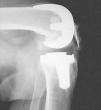

Realizamos una osteotomía del polo distal rotuliano, incluyendo superficie articular (fig. 5). Usamos el bisturí eléctrico para limpiar de restos óseos el tendón rotuliano. En los casos de artrofibrosis se produce un engrosamiento y metaplasia en el tendón rotuliano que hace que se pierdan los límites anatómicos normales de dicha estructura, apareciendo dicho tendón engrosado y englobado por una reacción fibrosa, por lo que realizamos la exéresis de tejido cicatricial, adelgazando el tendón mediante la extirpación longitudinal de las capas de fibrosis. De esta forma disminuimos la rigidez e incrementamos la longitud de dicho tendón, evitamos el posible roce del polo distal rotuliano con el labio anterior del polietileno y aumentamos el rango de flexión. Es el momento de evertir la rótula completamente; si no es posible se luxa lateralmente. Resecamos también la faceta lateral más marginal de la patela si es preciso, para evitar el roce de osteofitos con el cóndilo femoral. No realizamos la operación de Ficat si la rótula se encuentra centrada en las proyecciones de Merchant. Si flexionamos la rodilla aún más, accedemos a resecar todo el tejido periprotésico, LCP y cápsula posterior. Colocamos un implante de prueba sobre los dos tercios restantes de rótula. Una sobredimensión de 2-3 mm sobre el polo proximal rotuliano es aceptable, pero sólo fue necesario en nuestro primer caso, que resultó ser el más anquilosado. También se puede sobrepasar mínimamente el diámetro anteroposterior de la patela una vez protetizada con objeto de trasladar el tendón hacia delante, lejos del labio anterior del polietileno en flexión máxima (fig. 6). La convexidad de la rótula protetizada ayuda a impedir el roce del polietileno con el polo distal (fig. 7). La razón de no aceptar más de 2 mm de sobredimensión es que dudamos de la resistencia del hueso remanente en casos difíciles como estos4,9. Lo consideramos como límite de seguridad, teniendo en cuenta que hasta 5 mm no se ha relacionado con una mayor incidencia de fracturas de rótula, aflojamientos o pérdida de flexión3. Insertamos un nuevo polietileno del mismo grosor o inferior que el previo dependiendo de cada caso. En aquellos casos en que no había aflojamiento (tres primeros casos) se decidió no recambiar el componente femoral y elegimos un diseño de preservación del ligamento cruzado posterior con un LCP resecado. El principal motivo es evitar una cirugía agresiva que pueda conllevar más complicaciones10 de las necesarias. En el caso 3 se evitó colocar un polietileno ultracongruente debido a la gran prominencia de su labio anterior, específico de este diseño. En los casos 4 y 5 el recambio protésico era obligado por el aflojamiento previo. Esto permitió asociar otras opciones técnicas como la distalización de la interlínea.

Figura 7. Comprobación de la ausencia de roce con el polietileno.